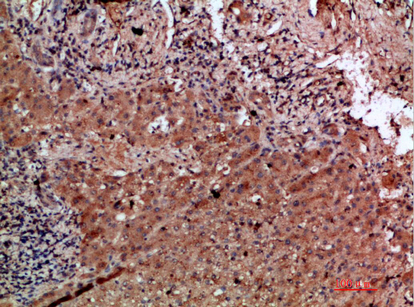

Immunohistochemical analysis of paraffin-embedded human-liver-cancer, antibody was diluted at 1:200

,